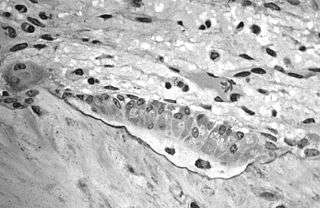

The underlying mechanism in all cases of osteoporosis is an imbalance between bone resorption and bone formation. In normal bone, matrix remodeling of bone is constant; up to 10% of all bone mass may be undergoing remodeling at any point in time. The process takes place in bone multicellular units (BMUs) as first described by Frost & Thomas in 1963.[74] Osteoclasts are assisted by transcription factor PU.1 to degrade the bone matrix, while osteoblasts rebuild the bone matrix. Low bone mass density can then occur when osteoclasts are degrading the bone matrix faster than the osteoblasts are rebuilding the bone.[75]

Trabecular bone (or cancellous bone) is the sponge-like bone in the ends of long bones and vertebrae. Cortical bone is the hard outer shell of bones and the middle of long bones. Because osteoblasts and osteoclasts inhabit the surface of bones, trabecular bone is more active and is more subject to bone turnover and remodeling. Not only is bone density decreased, but the microarchitecture of bone is also disrupted. The weaker spicules of trabecular bone break ("microcracks"), and are replaced by weaker bone. Common osteoporotic fracture sites, the wrist, the hip and the spine, have a relatively high trabecular bone to cortical bone ratio. These areas rely on the trabecular bone for strength, so the intense remodeling causes these areas to degenerate most when the remodeling is imbalanced. Around the ages of 30–35, cancellous or trabecular bone loss begins. Women may lose as much as 50%, while men lose about 30%.[28]